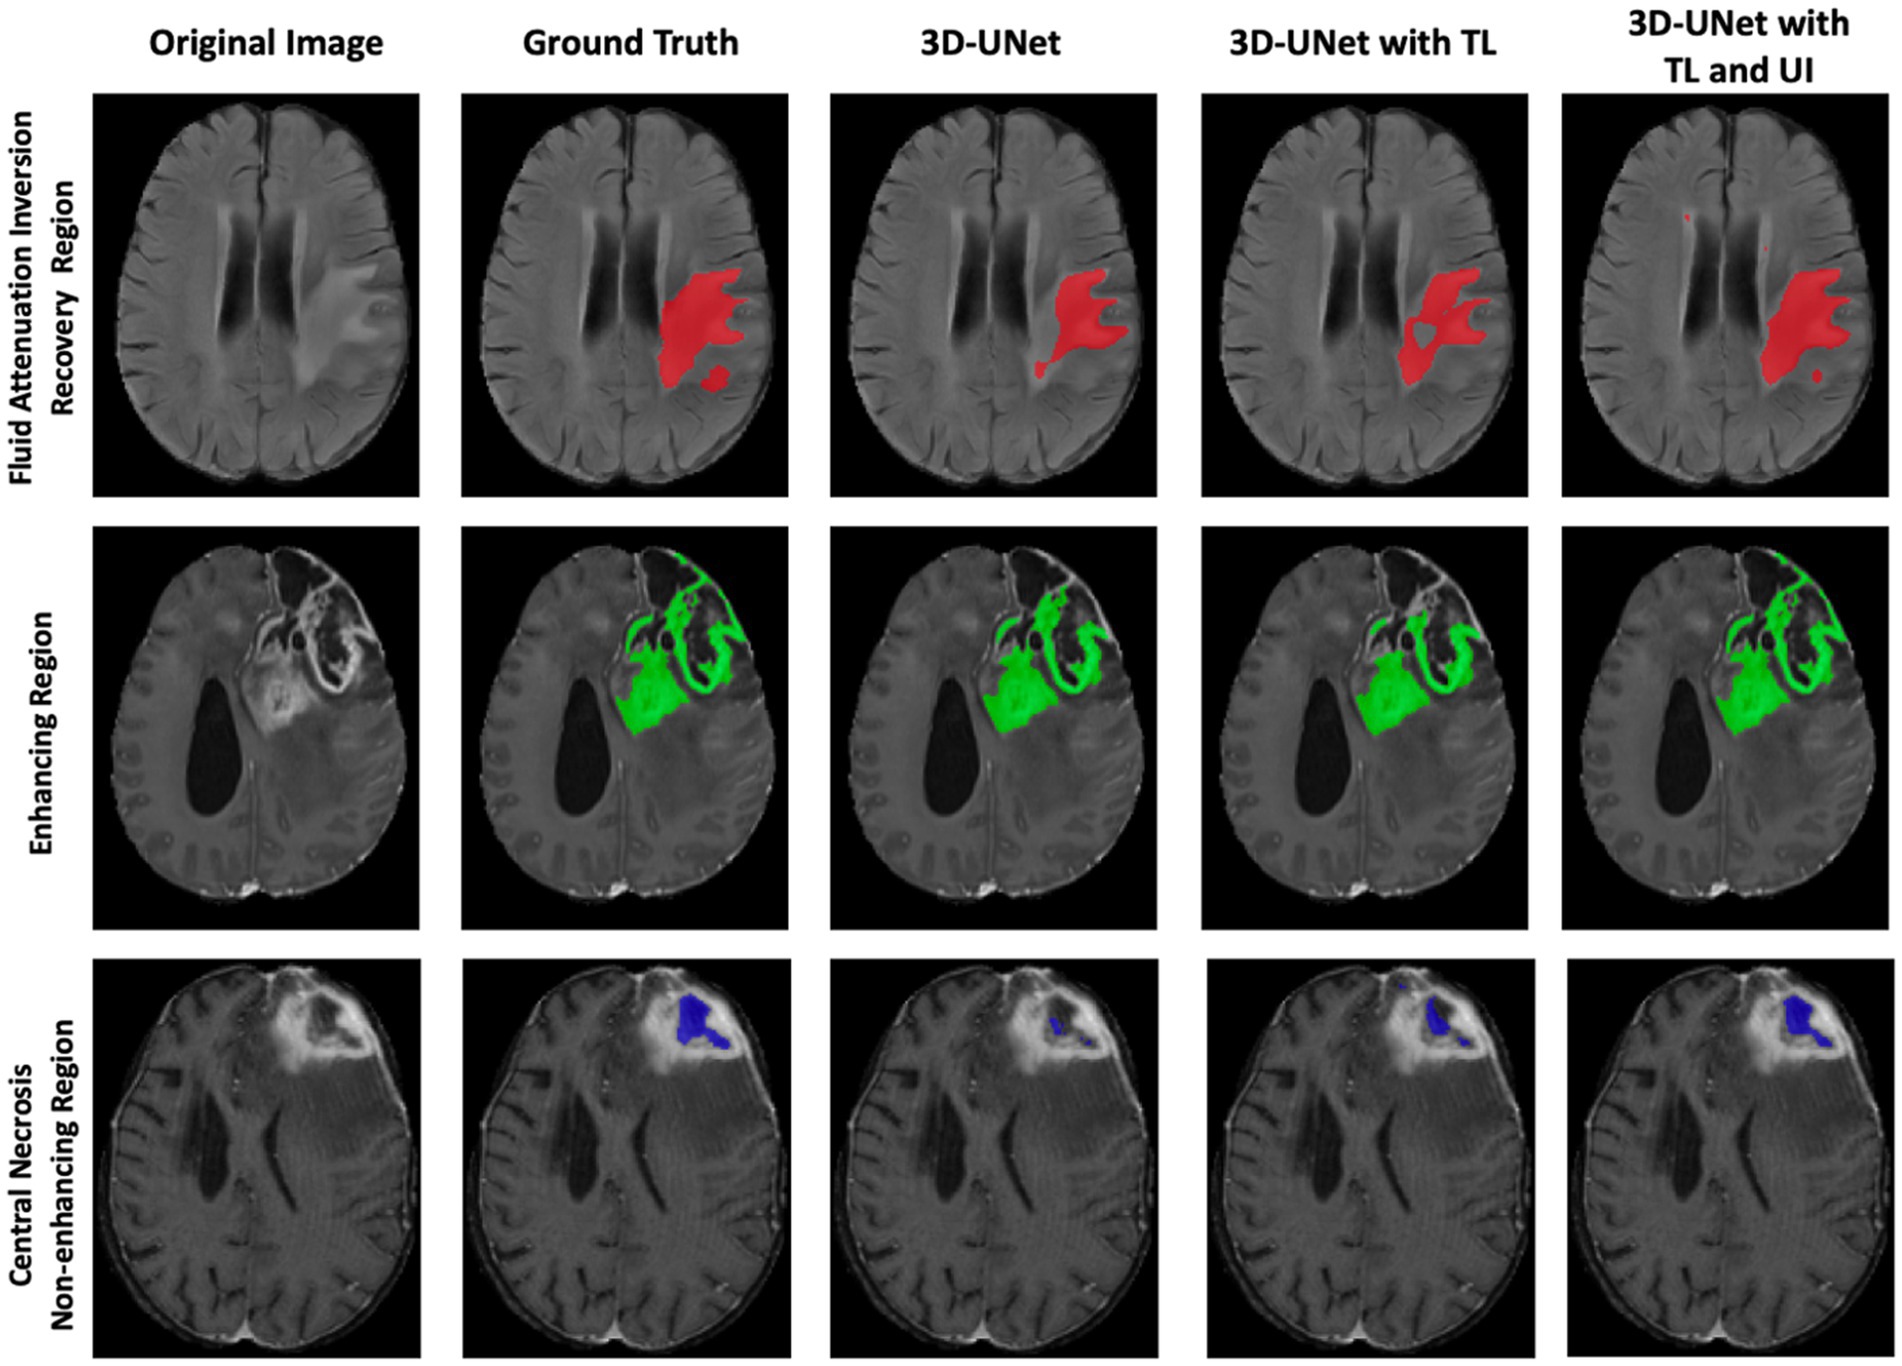

Figure 5 visually demonstrates the improved performance using transfer learning and uncertainty information for three cases. In each case, some regions are misclassified by either the 3D U-Net or the 3D U-Net with transfer learning. However, the 3D U-Net with uncertainty and transfer learning consistently provides more accurate segmentation and reduces misclassification compared to the other models.

Figure 5. Comparison of 3D-UNet models for brain tumor segmentation. Columns show the original MRI, ground truth, baseline 3D-UNet, 3D-UNet with transfer learning (TL), and 3D-UNet with TL and uncertainty information (UI). Rows correspond to the FHR region (red), ER region (green), and NENR region (blue). Incorporating TL improves boundary delineation, while TL combined with UI reduces false positives and enhances agreement with ground truth. These results demonstrate that transfer learning and uncertainty information together yield more reliable and generalizable tumor segmentation across multiple patients’ MRIs.